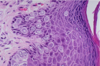

Normal Breast Tissue

Immunoperoxidase stain with antibody to actin demonstrates the myoepithelial cell layer around the breast acinus. The myoepithelial cells are contractile and are very sensitive to oxytocin.